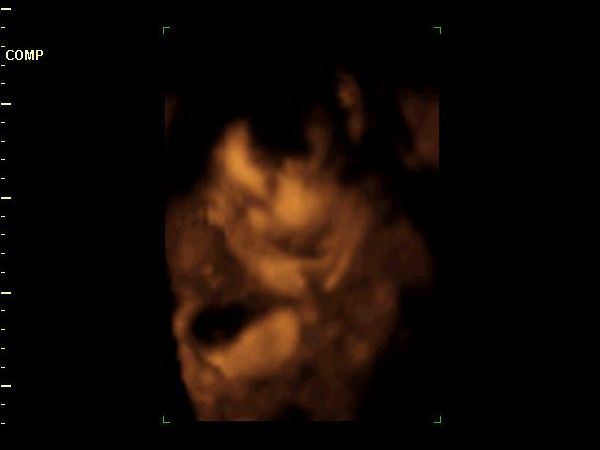

Zsebi, mindig elfelejtem írni neked a Lézert. Mi ott voltunk 2x, nagyon kedvesek voltak. Nellykém elbújt, nem mutatta magát, de a nőci nagyon kitartó volt és a fél óra helyett lett 1 órás felvételünk . Teszek fel neked pár 4D-s képet.

28 hetes Nelly